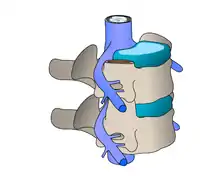

Disque intervertébral

Un disque intervertébral (DIV) ou fibrocartilage intervertébral est un cartilage qualifié de fibreux, qui se trouve entre presque toutes les vertèbres de la colonne vertébrale (sauf entre C1/C2). Chaque disque est formé d'un fibro-cartilage mixte (se rapprochant d'une symphyse), et permet un faible mouvement des vertèbres. Il agit aussi comme un ligament maintenant les vertèbres ensemble. Son rôle d'amortisseur des chocs est crucial et son altération physiologique explique les nombreuses pathologies du dos.

Structure et origine chez l'Homme

Les disques intervertébraux sont constitués d'un anneau fibreux externe, l'annulus fibrosus, qui entoure une substance gélatineuse interne, le nucleus pulposus[1].

- L'anneau de cartilage fibreux (en latin : annulus fibrosus) se compose de plusieurs couches (lames) de fibrocartilage constitué de collagène de type I et de type II. Le type I est concentré à l'extérieur de l'anneau conférant une grande solidité.

- Il provient embryologiquement du sclérotome, dérivé des somites.

- Le noyau gélatineux ou noyau pulpeux (en latin : nucleus pulposus) permet lui de distribuer uniformément la pression sur tout le disque et empêche le développement de contraintes qui pourraient endommager les deux vertèbres sous et sus-jacente. Le nucleus pulposus contient des fibres en suspension dans un gel de mucoprotéine. Le noyau du disque agit donc comme l'absorbeur des chocs engendrés par l'activité physique de l'organisme et empêche les impacts entre les vertèbres.

- Il s'agit d'un vestige embryologique de la notochorde[2].

Schéma vertèbre et disque intervertébrale